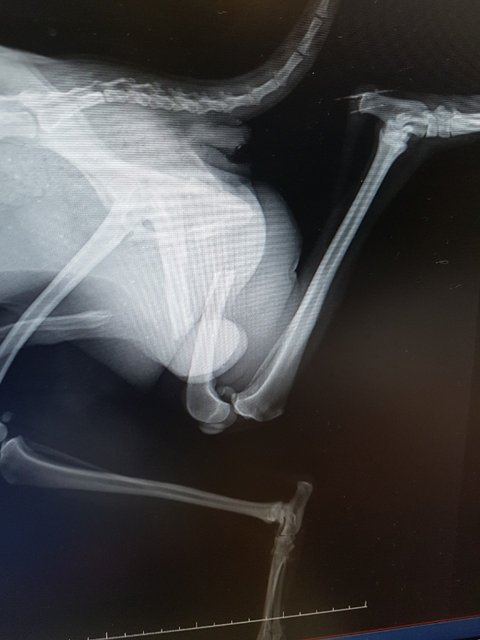

외진 주유소에 아픈다리를 끌고 들어와 나가지않고 한곳에만 움크리고 있다며 신고로 들어오게 됐습니다.

등골이 만져질정도로 비쩍마른몸과 덜렁거리는 다리를 들고 힘겹게 견디었을 녀석이 안쓰럽기만 합니다.

대퇴골 골절..

천사님의 도움으로 수술을 무사히 받고 사상충치료까지 받을수 있었던 츄츄는 몸도 마음도 건강해졌습니다